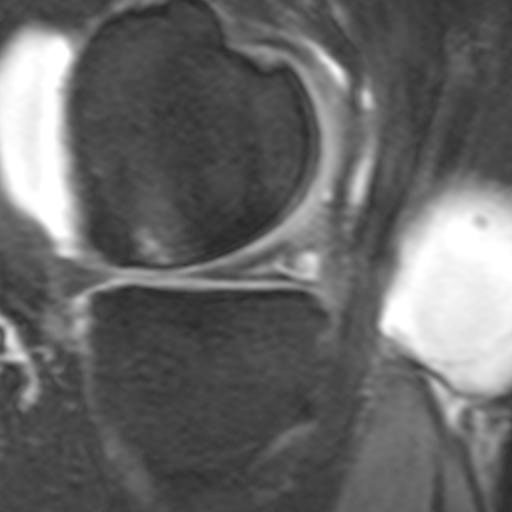

Kniegelenk Meniskusruptur Klinik Am Ring

Kniegelenk Meniskusruptur Klinik Am Ring from klinik-am-ring.de